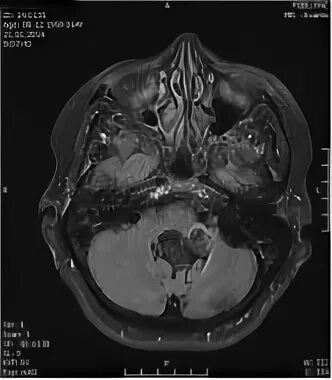

Мрт головного мозга мосто мозжечкового угла